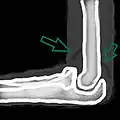

Joint effusion

A traumatic right knee effusion. Note the swelling lateral to the kneecap as marked by the arrow.